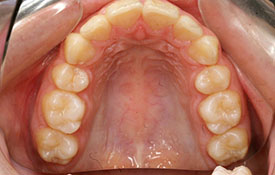

インビザラインの治療例:CASE-1

| プロフィール | 42歳 女性 |

| 所見 | 他院で行われた矯正歯科治療後の後戻りに悩まれて来院されました。 アイライナーの装着は、1日平均20時間ほどでした。 |